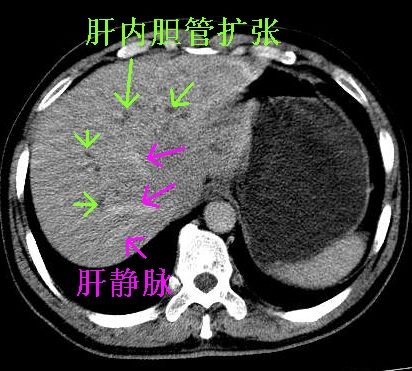

首先,胆总管下端结石梗阻伴肝内胆管扩张可确定。

其次,增强动脉期肝静脉显影,肝实质密度不均。——此为右心功能不全引起肝淤血的表现。

另外,肝八段低密度占位,呈多灶性,考虑肝脓肿或肝癌可能,(图像质量欠佳)建议进一步检查。

胆总管及肝内胆管扩张,考虑是结石!但,肝内的低密度区增强不明,可能是肝ca,因为肝ca在增强时呈快进快出.另年胆总管扩张原因,可以考虑一下是不是,胆管ca.再次要考虑肝内的低密度是否为海绵状血管瘤所致!